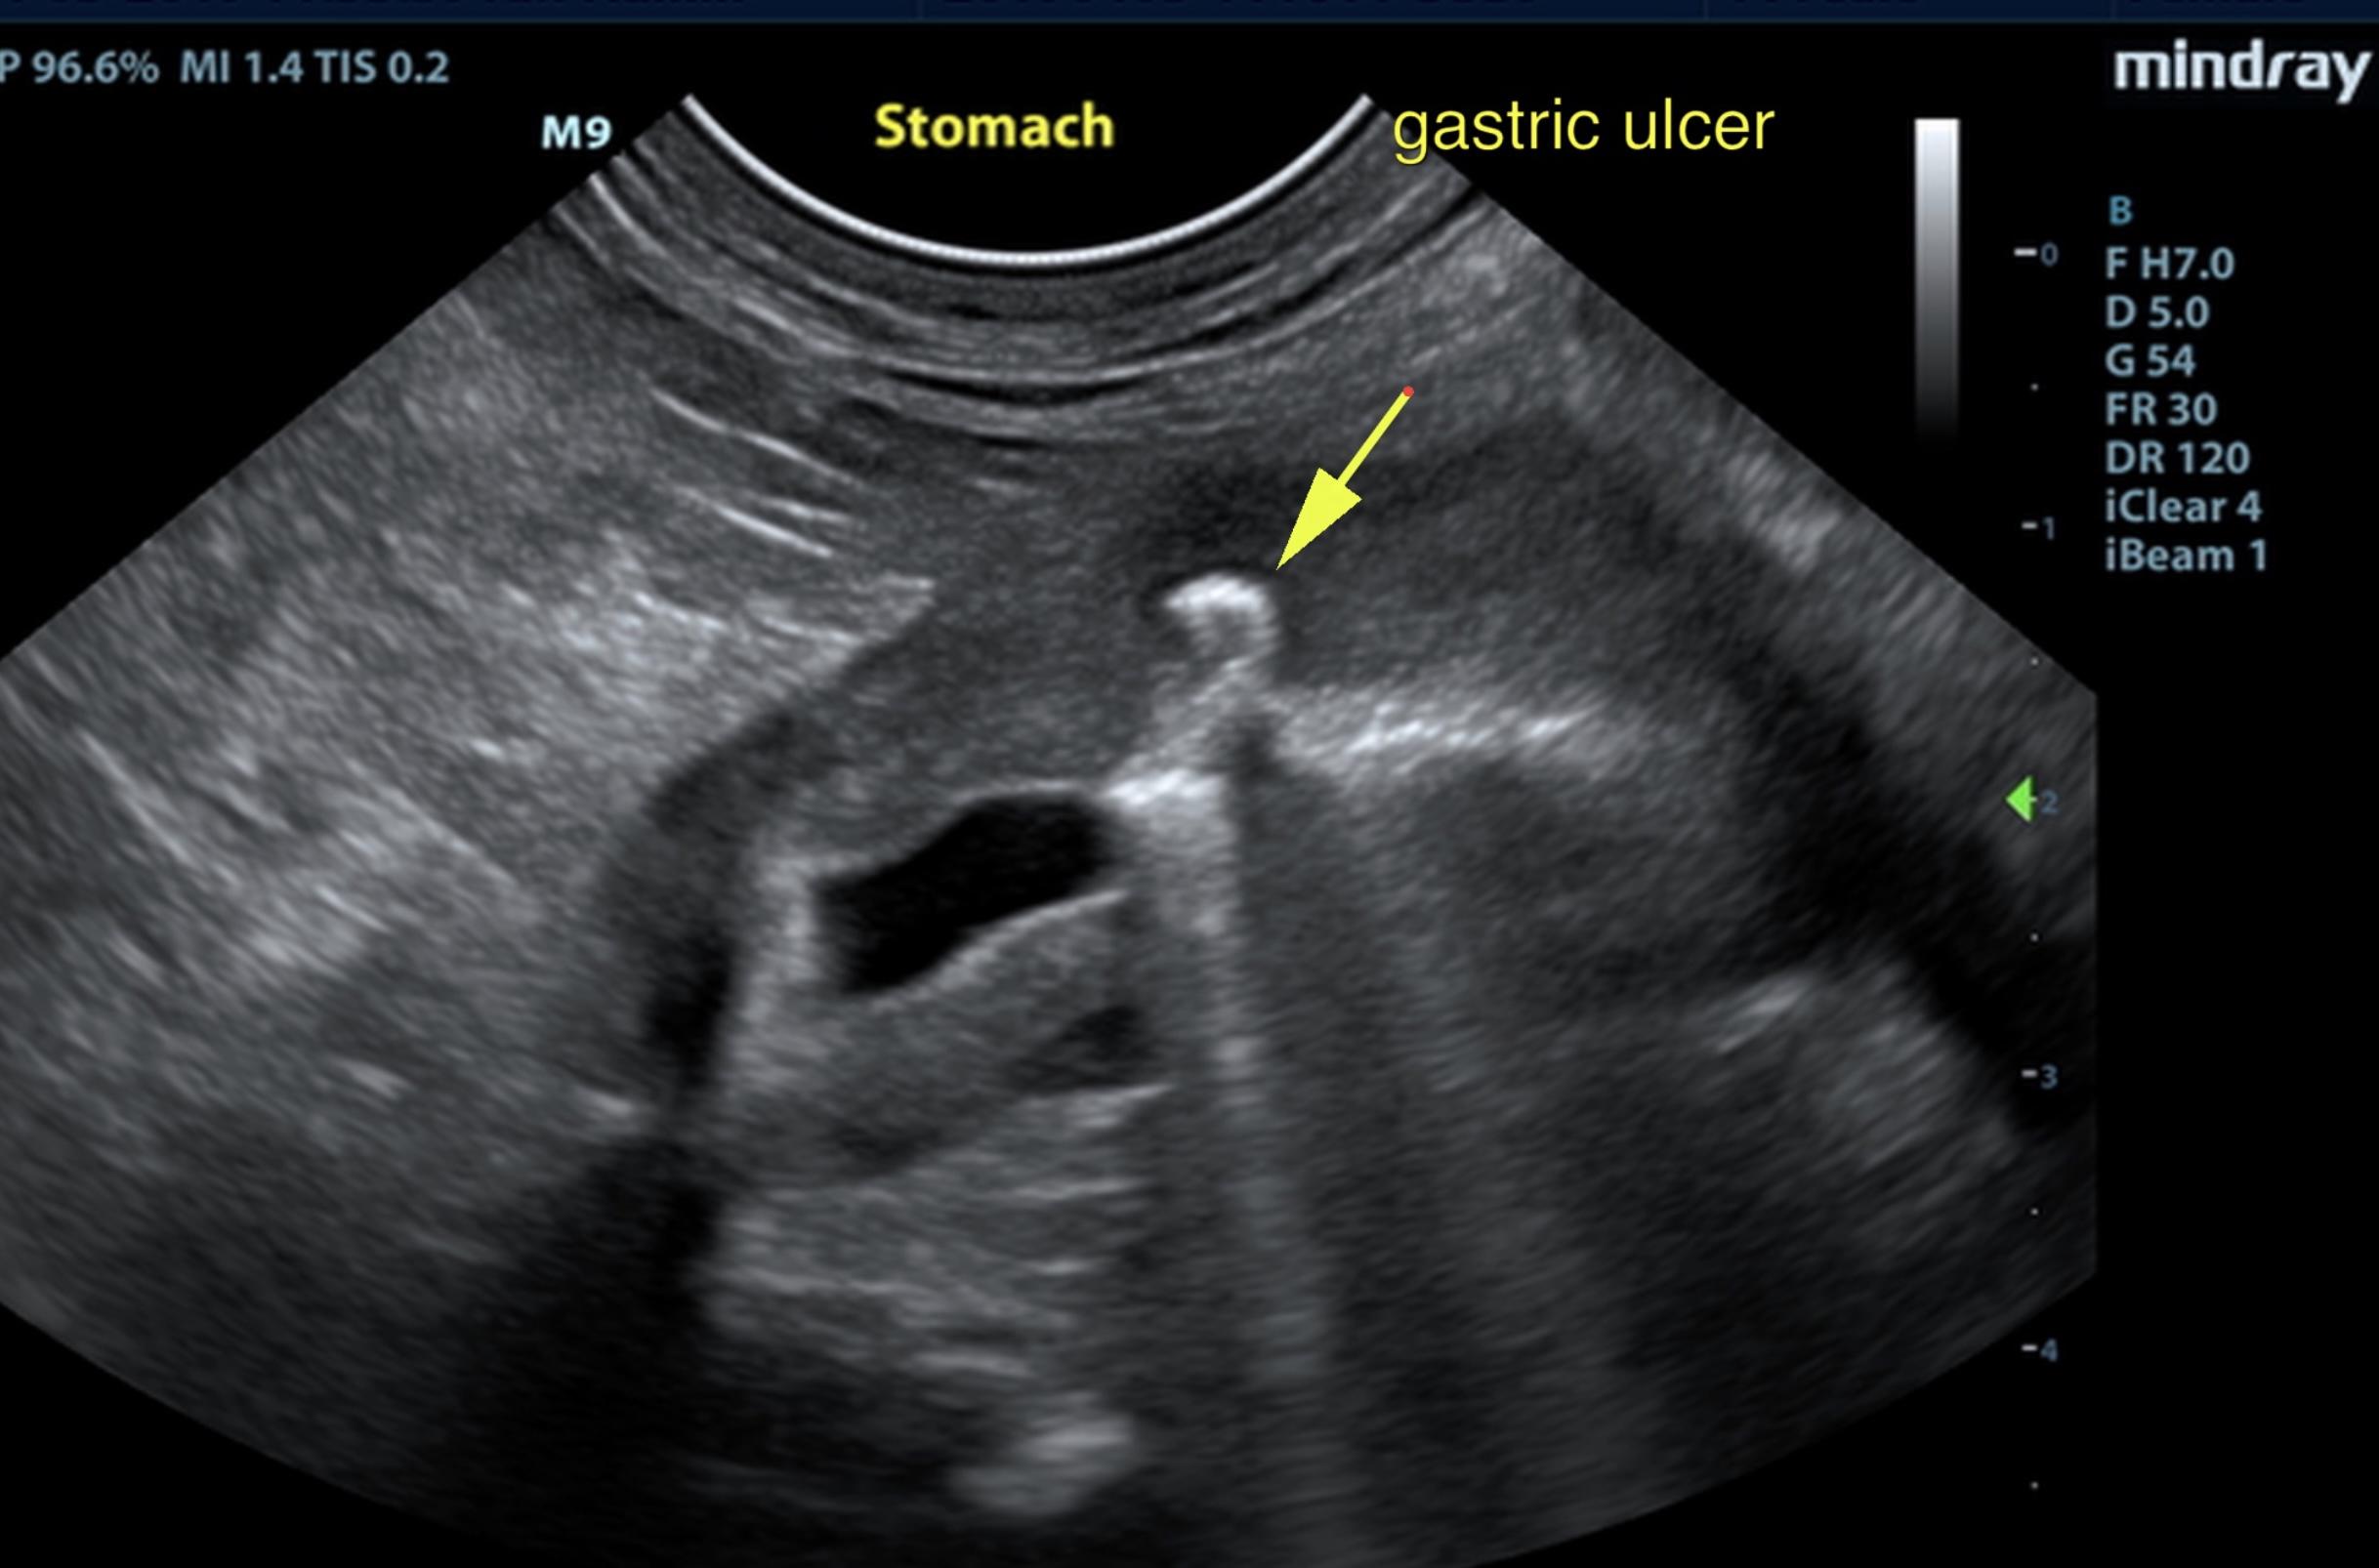

duodenal ulcer? 11/9/23